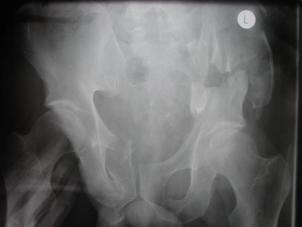

Banda de stabilizare Dallas Fractura de bazin. Radiografie in

incidenta AP

Fractura de bazin

. Radiografie in incidenta AP Fractura de spina